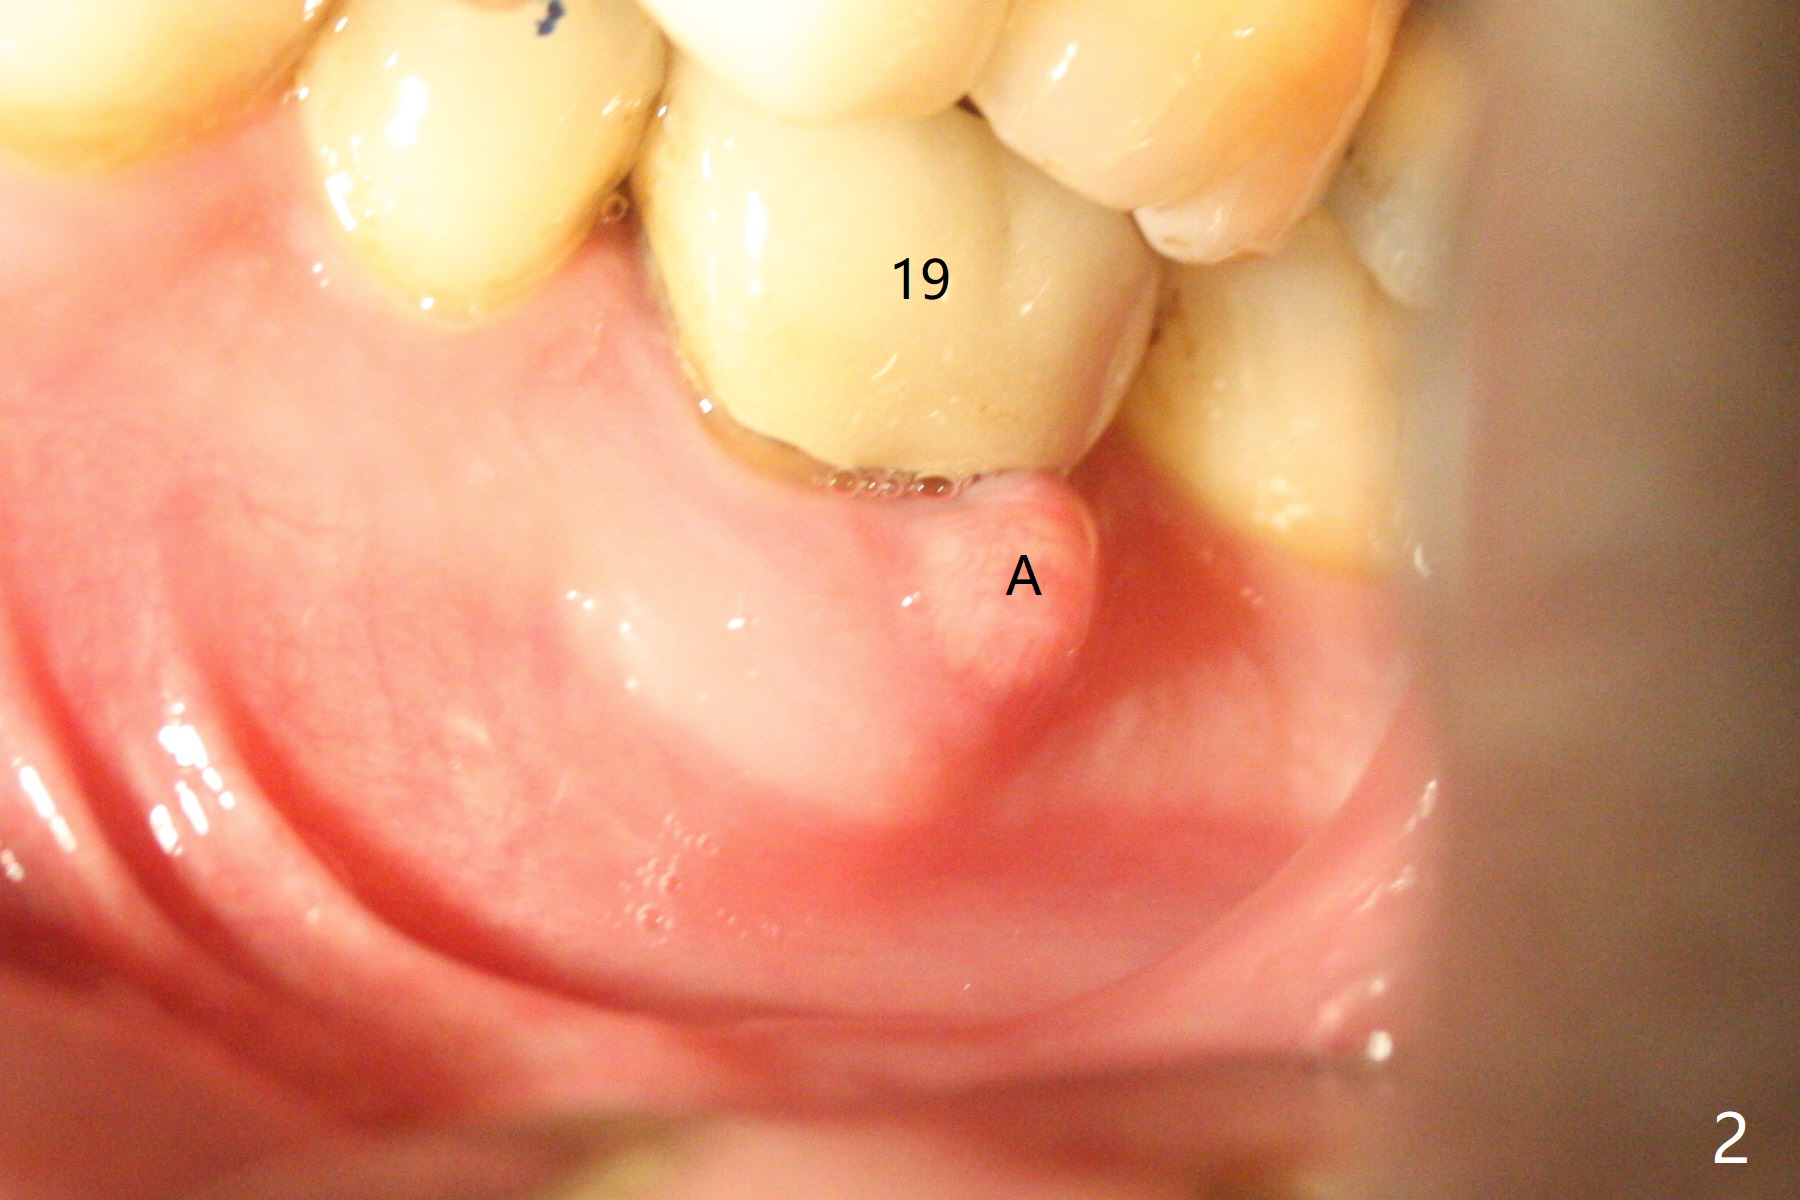

When the patient returns for #15 comp, the bone resorption and swelling at #19 are worse than those 3 years ago (Fig.1,2). After debridement, the mesial socket is large, while the septum is thin, irregular and with undercut (Fig.3). It seems difficult to obtain primary stability for an immediate implant. Vanilla bone and cortical bone hydrated with GEM21 S are placed for socket preservation (Fig.4,5), followed by 12x12 mm BioXclude and 4/0 PGA. In fact the bone height is limited for an immediate implant (Fig.6 (5x10 mm)). There is not enough bone in the septum for primary stability (Fig.7 (cross section of 3D image; L: lingual)). The socket heals 16 days postop (Fig.8). It appears that the granulation tissue is covered by a thin layer of granulation tissue (Fig.9 *), while the membrane remains in place (M). In fact the bone graft remains in the soft tissue zone as well as the hard tissue one (Fig.10). In spite of no apparent loss of bone graft (Fig.4,10), the graft seems to shrink in height 3.5 months postop (Fig.11), while the crest decreases (compare Fig.1 and 11). The keratinized gingiva is wide, but the alveolus reduces in width (Fig.12). The buccal crestal bone is lost 3.5 months postop (Fig.13).